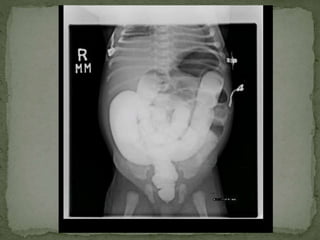

 Barium enema single contrast study- 18th June, 2013

 Moderate distension of large bowel without definite

haustral pattern

 May represent distal segment Hirschsprung disease

 Findings can also be seen in constipation and myxdema

 Barium enemasingle contrast study- 18th June, 2013  Moderate distension of large bowel without definite haustral pattern  May represent distal segment Hirschsprung disease  Findings can also be seen in constipation and myxdema